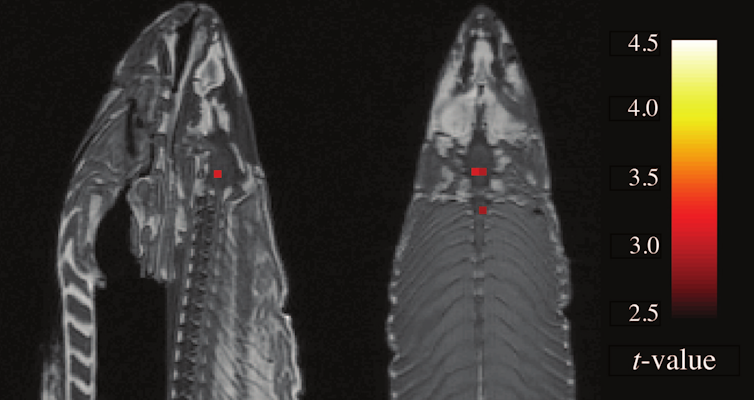

The pattern of changes differs when you believe you play a person as opposed to when you believe your opponent is a computer.

Subtract the patterns from each other, do some more statistics, and the result is a neat coloured blob on a picture of the brain.

Since the only real difference between the playing conditions is your mental state, the difference in brain activity must be specific to that type of mental state.

So the blob signifies the part of the brain that explains why we interact differently with people and computers.